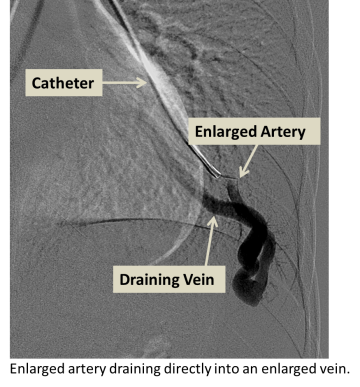

Arteriovenous malformations (AVMs) refer to arteries and veins with abnormal connections between them. In the lungs, arteries first carry blood from the heart to smaller arteries which then feed into even smaller vessels called capillaries. Capillaries, which are within organs, slow down blood flow and allow for nutrient and gas exchange between the blood and organs. Veins carry blood away from capillaries and back to the heart.

In the presence of an AVM, the arteries and veins are directly connected without intervening capillaries, reducing gas exchange and causing decreased oxygen levels and shortness of breath, especially with exertion. The abnormal arteries and veins in an AVM often have weak walls, and bleeding into the lung can result. Clots or bacteria in the lung circulation that would normally get trapped in small capillaries can pass through the AVM to the blood vessels of the brain and cause stroke or brain abscess.

- Angiography (X-ray with contrast agent to visualize and treat the abnormal blood vessels)